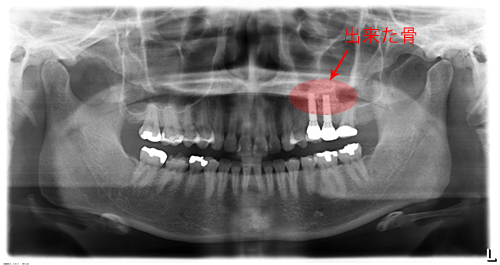

左上の奥歯の骨が少なくてそのままではインプラントを入れられなかったため、オペと同時にサイナスリフトをしました。

今ではしっかり噛めています。骨が極度までない場合でもほとんどがインプラントオペと同時にサイナスリフトが可能です。